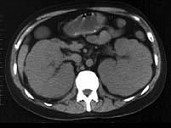

- 多项选择题男,38岁, 进行性肾衰竭,有淋巴瘤病史, 行腹平片、CT及MRI检查如图所示,下列说法正确的是 ( )

A、CT示双肾对称性增大

椎体可见局灶性低信号改变C、考虑为肾淋巴瘤,且淋巴瘤累及L

椎体D、考虑为多囊肾

E、考虑为肾炎